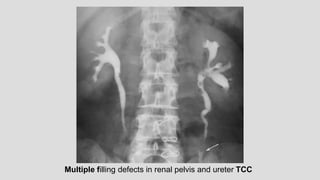

Multiple filling defects in renal pelvis and ureter TCC